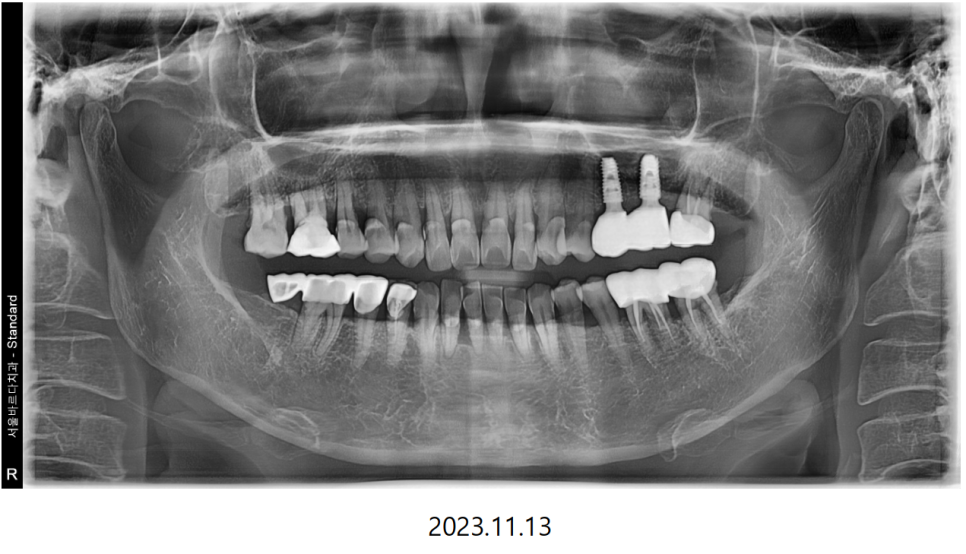

임플란트와 뼈이식한 재료들이 단단하게 아문 뒤

치아의 본을 떠 임플란트의 기둥과

치아의 머리 부분인 크라운을 제작하게 됩니다.

스캐너로 픽스처와 잇몸의 위치를 잘 채득한 덕분에

맞춤기둥과 크라운을 잘 맞게 만들어 올 수 있었고

기둥을 체결 한 다음 보철을 올려 확인해 보니

맞물림도 잘 맞아서 바로 붙여드릴 수 있었습니다.

위와 같은 과정을 통해 성공적으로 임플란트를 완료하셨습니다.

위 아래 높낮이에 잘 맞춰서 제작해드린 덕분에

식사하시는것도 양쪽 다 똑같이 편안하다고 말씀하셨는데요